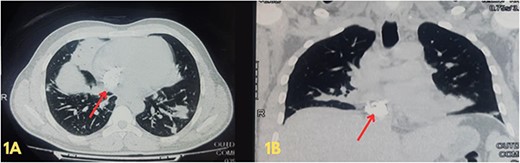

Blood investigations revealed leukocytosis and thrombocytopenia (Table 1). His electrocardiogram (ECG) showed a normal sinus rhythm, and chest X-ray revealed bilateral infiltrates. A high-resolution computed tomography (HRCT) scan of the chest was done in February 2020, which showed multiple patchy pulmonary infiltrates in the upper and lower lobe of the left lung, the middle lobe and the lower lobe of the right lung (Fig. 1). An air bronchogram was noted within the area of consolidation of the middle lobe of the right lung. Also, heavy calcification of irregular areas within the right atrium, extending up to the opening of the IVC, was noted. We did a further investigation with transthoracic echocardiography, which revealed an echogenic mass in the right atrium of 3.0 ✕ 1.9 cm2, most likely a thrombus. Following this, we investigated the patient with cardiac MRI, which showed a large irregular mass of 25 ✕ 18 mm2 in the right atrium attached to the interatrial septum and extending to the IVC, most likely myxoma with superimposed thrombus (Fig. 2).

(A and B) Axial and coronal views of a high-resolution computed tomography scan of the chest showing multiple opacifications in the lung field and heavy calcification within the right atrium, extending up to the opening of the inferior vena cava.